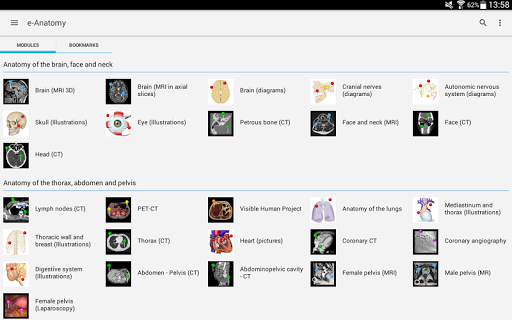

New : You can now filter the modules by region or by content type so you can find the module you are looking for much faster.

-Two new modules : Brain - TOF and Brain Angiography, Atlas of normal neurovascular anatomy of arteries of the brain on a cerebral angiogaphy.-The interface has been reworked.-A new tab named "QuickLinks" is available, dispatching modules in sections of the human body and allowing you to fast travel to the modules you are looking for.-Fixed small bugs.